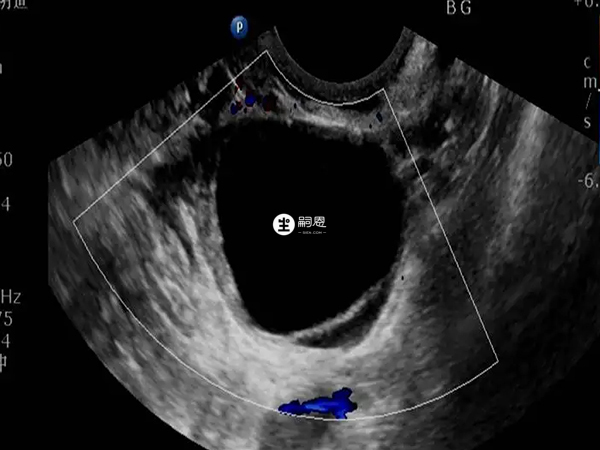

一般來說,卵泡黃素化b超能看出來。正常的成熟的卵巢排出之後,子宮直腸窩會出現少量的遊離性液體。如果卵巢持續不消失或繼續增大,這就要考慮卵巢會破裂,出現卵泡黃素化。卵泡黃素化一般主要是通過陰道b超可以看出來,當卵泡長大到25mm,如果檢測還沒有排卵,那可能就是卵泡黃素化,但是有的人優勢卵泡就是比較大,排卵晚一些,所以B超如果看到卵泡長到25mm就沒有監測了,可能會出現誤判。還有就是可以結合人尿中黃體生成素的檢查來確定,也可以結合基礎體溫來進行判斷,抽血化驗看雌孕激素水平也可以,但無論是哪種方式,都不能做到100%準確。

卵泡黃素化就是卵泡不破不排卵而原位黃素化,而卵泡黃素化和排卵都會引起身體的激素水平發生變化,所以通過抽血化驗激素水平看是否排卵,也就可以判斷卵泡是否黃素化。下面是整理的判斷卵泡黃素化的方法: